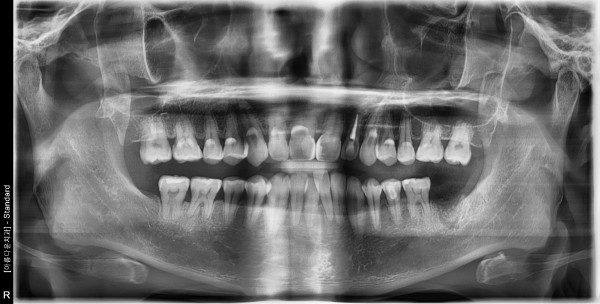

41세 남/ 하악 좌측 어금니 발치 및 치조골이식술 후 임플란트 식립